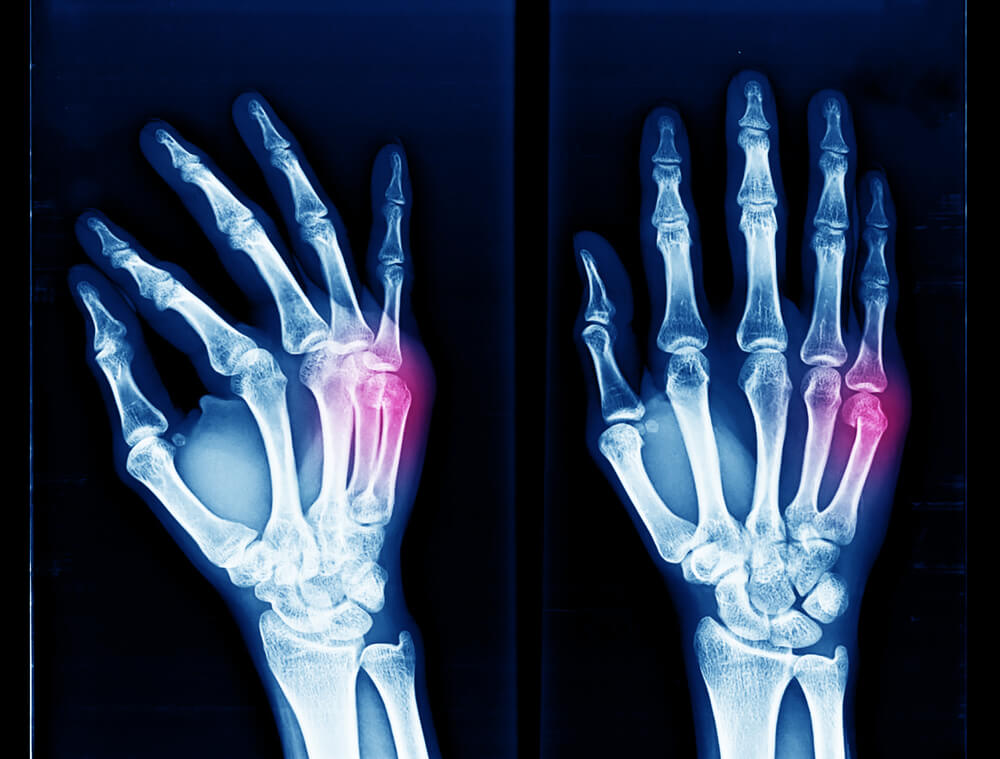

Why Does My Boxer’s Fracture Still Hurt?

- Delayed Union or Nonunion: In some cases, fractures may experience delayed union (taking longer to heal) or nonunion (failure to heal). This can occur if the bone ends do not properly join together or if there is inadequate blood supply to the fracture site.

- Misalignment or Malunion: If the fractured bone does not heal in proper alignment, it could lead to ongoing pain and functional limitations.

- Nerve Irritation: Fractures can sometimes irritate surrounding nerves, causing pain after the bone heals.